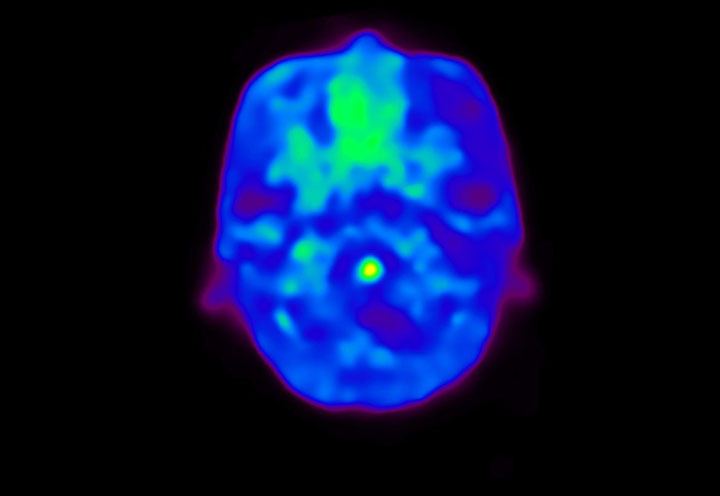

Head / Case4 : Amyloid

Axial

Courtesy : Kindai University Hospital

- Imaging protocol

- Injected dose: 3.21 MBq/kg, 18F-Flutemetamol

- Uptake time: 100 minutes

- Scan time: 20 minutes